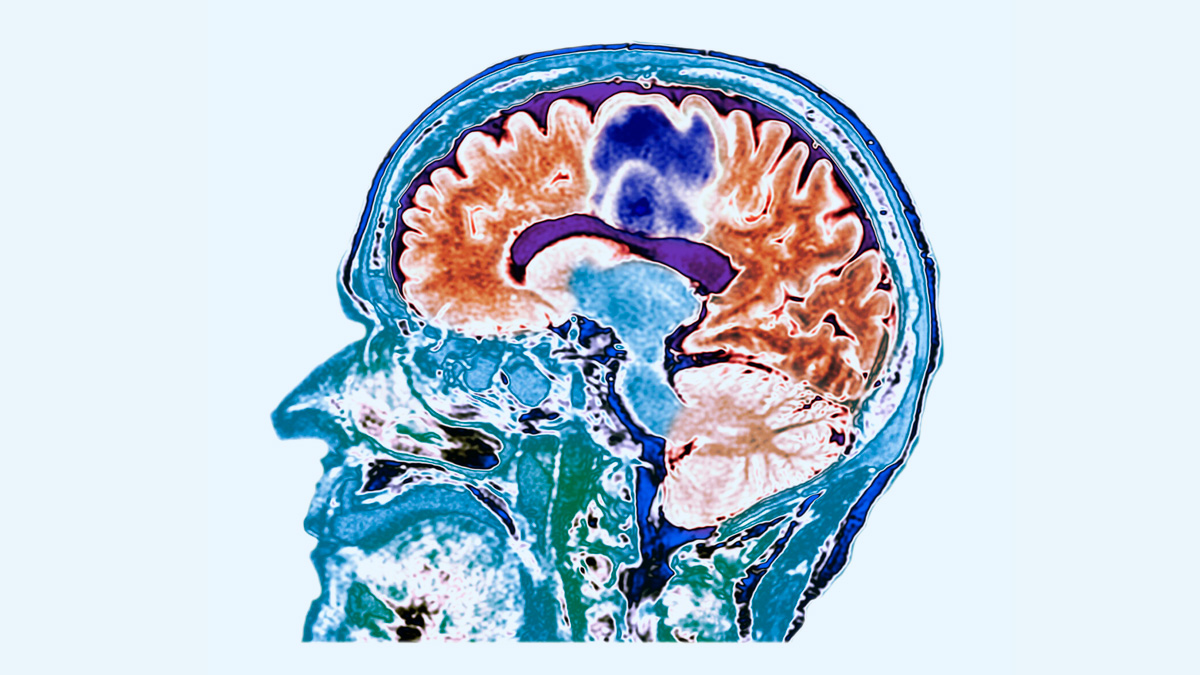

Glioblastoma is a type of brain cancer that starts in the brain’s supportive cells called astrocytes. It is classified as a grade 4 tumour, which means it is the most aggressive and fast-growing form of brain cancer. Dr BSV Raju, Senior Consultant Neuro and Spine Surgeon, Yashoda Hospitals, Hyderabad, explains, “Glioblastoma, a lethal, complex, and treatment-resistant cancer, constitutes over 50% of adult cases of cancerous brain tumours. It is a malignancy that begins with the development of cells in the brain or spinal cord, grows rapidly, and can invade and destroy healthy tissue.” This cancer can occur in any part of the brain, but is most often found in the frontal and temporal lobes.

Glioblastoma is one of the deadliest cancers because it grows very fast and spreads into healthy brain tissue. Unlike some tumours that form a clear mass, glioblastoma has ‘tentacles’ that invade surrounding areas. It makes it nearly impossible to remove completely through surgery. Even after surgery, microscopic cancer cells remain, which often cause the tumour to grow back. The average survival time after diagnosis is about 12 to 18 months, despite aggressive treatment.